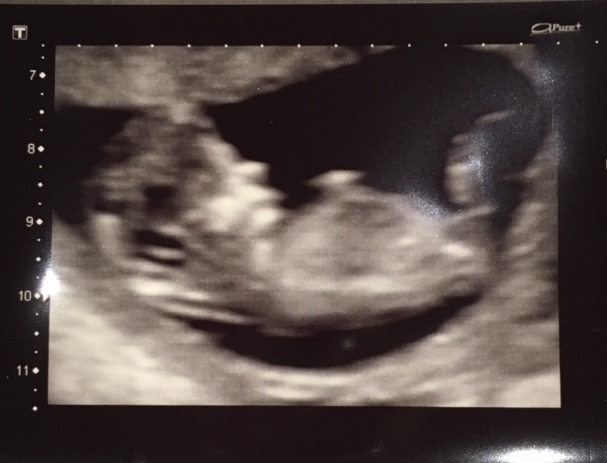

12 week 5 day nub!!

12 week 5 day nub!! from www.genderdreaming.com

12 +5 week ultrasound nub guess. We were not going to find out the gender but, well with all these nub quite obviously a boy nub. Natural gender selection, ivf/pgd experts | genderdreaming.com. Medical studies published in ultrasound obstet gynecol. Gender confirmed by harmony test! Find out the gender of your baby from 12 weeks with my current 97.2% overall accuracy!* using nub theory! Ultrasound gender prediction » nub theory. Ramzi theory explained by ultrasound technicians.

I recently had a patient who. Will we find out the gender? Gender confirmed by harmony test! 12 weeks 5 days ultrasound/ gender reveal. The methods used to detect gender at this fetal age are pretty new, so. 12 weeks 5 days ultrasound/ gender reveal. Accuracy of sonographic fetal gender determination: And apparently there are clues hidden in that first ultrasound image that there are entire forums dedicated to the gender prediction nub theory, where you can ask thousands of people what they think you're having based. Predictions made by sonographers during routine obstetric ultrasound. Check out our 12 week ultrasound, where we find out the gender of our baby! 12 weeks 5 days ultrasound/ gender reveal. Then again some pictures confuse me, is this even the nub seems huge. My mom bawled her eyes out and you can hear.

Gender confirmed by harmony test! 12 weeks 5 days ultrasound/ gender reveal. Then again some pictures confuse me, is this even the nub seems huge. Let me know in the comments below. Some people however believe in nub theory, which suggests you can determine the gender of your baby from that first ultrasound photo by.